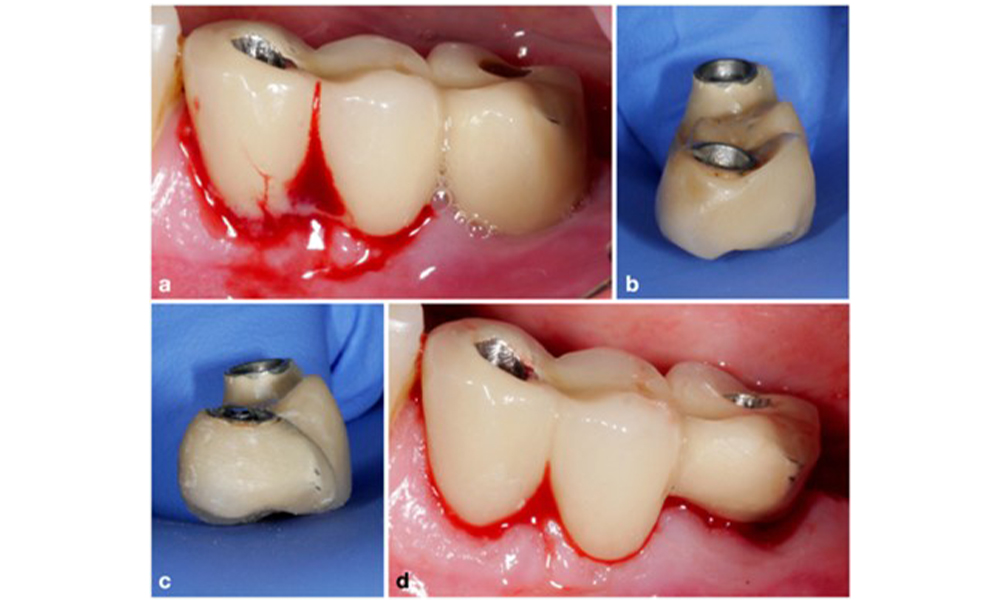

Since the primary etiologic factor for peri-implant biological complications is the oral biofilm, two crucial aspects should always be considered as integral part of the treatment independent of a diagnosis of peri-implant mucositis or peri-implantitis: (1) the level of oral hygiene, and (2) the cleanability of the prosthetic restoration (figure 4).

Thus, both the patient's oral hygiene routines and the prosthetic restoration’s design and implant positioning should support effective cleaning. If required, adjustments to the existing restoration (figure 5) and specific instructions for tailored oral hygiene measures are essential (figure 6) (Hamilton et al. 2023; Jepsen et al. 2015).